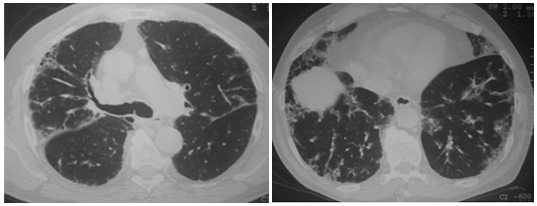

Sebastián Lamot: La tomografía computada

(TC) de tórax de 2010 mostraba, principalmente,

engrosamiento reticular sub-pleural, de predominio en bases y en lóbulo inferior derecho. Se observaban áreas con vidrio esmerilado bilateral,

parcheadas. Se puede describir patrón de panalización, caracterizado por quistes dispuestos –en

empalizada–, compatible con neumonía intersticial

usual (UIP) definitiva1, 2.